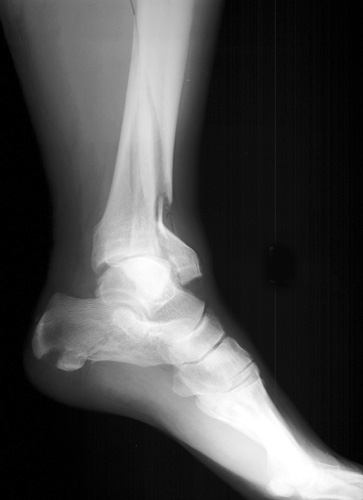

Lateral views of calcaneal fractures

Now look for the calcaneal fracture (and other abnormalities) in the image below. Can you find them? Click on the image for the answer.

Lateral view